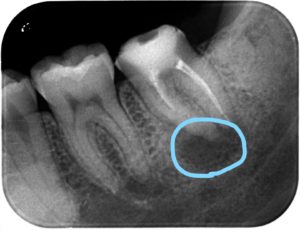

レントゲン撮影を行ったところ、

下の青丸の個所が黒くなっているのがわかるでしょうか??

この歯は以前、神経を取り除き、空洞になった神経の部屋に白い薬を詰めて、蓋がしてある歯でした。

しかし経年的に中に入っているお薬が劣化し、溶け出てしまった結果、中で感染を起こし根っこの先に膿が溜まってしまっています。

こうなると、噛むと痛い、などの症状が出やすくなります。